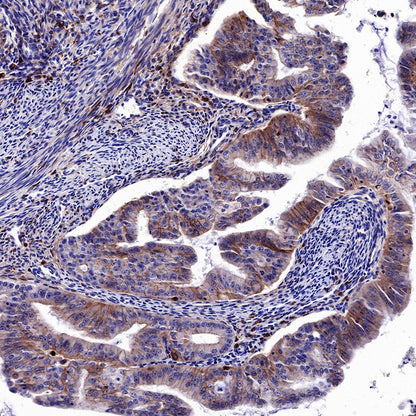

IHC shows positive staining in paraffin-embedded human colon. Anti-EGFR antibody was used at 1/2000 dilution, followed by a HRP Polymer for Mouse & Rabbit IgG (ready to use). Counterstained with hematoxylin. Heat mediated antigen retrieval with Tris/EDTA buffer pH9.0 was performed before commencing with IHC staining protocol.